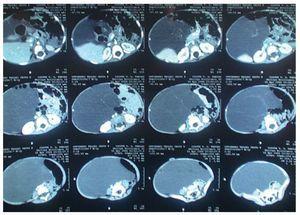

Inició su padecimiento 6 meses previos, con rechazo al alimento y distensión abdominal. Es llevado a centro de salud donde le prescriben hierro y vitaminas A, C y D. En el último mes se agregaron evacuaciones líquidas color verdoso, con moco. Se manejó con electrolitos orales, remitiendo el cuadro. Su médico de primer contacto solicitó estudios de laboratorio, los cuales registraron anemia microcítica e hipocrómica. Además, el ecosonograma abdominal mostró masa quística intra-abdominal multilobulada extendiéndose por ambas correderas y hueco pélvico. Riñones, hígado y vesícula biliar se presentaron sin alteraciones (fig. 1).

Figura 1 Se tomó estudio con equipo Medison de alta resolución, con transductor convexo. Se observó una imagen de aproximadamente 12.2 x 6.8 cm, de aspecto anecoico multitrabeculado.